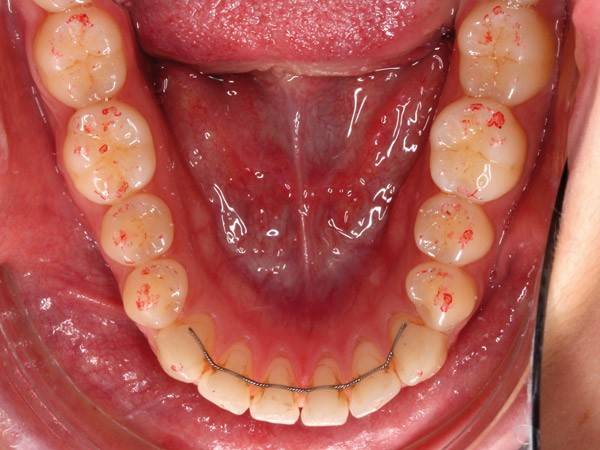

Ces différents aspects dépendent non seulement de la qualité et de l’épaisseur du papier, de son support, de la composition de l’encre, de l’imprégnation salivaire, mais aussi de la force de morsure [3-8]. En fonction du nombre de morsures et de la manière dont le patient serre sur le papier à articuler, la couleur, la taille et la forme des marques varient (fig. 1).

De plus, son utilisation répétée réduit significativement la précision et la sensibilité [4]. Même lorsque ces papiers sont employés dans des conditions idéales, les marques ne sont pas reproductibles [2-5, 9, 10] et le papier à articuler est souvent sujet à des perforations ou des déchirures lors des mouvements de fermeture en intercuspidie [9]. D’autre part, sur un champ humide, l’encre peut diffuser, ou le papier peut se plier, par exemple par retour du papier occlusal…